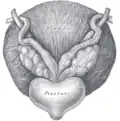

Vesículas seminales vistas en un espécimen cadavérico desde arriba, con la vejiga en la parte inferior de la imagen y el recto en la parte superior. Se aprecia su posición cerca de los conductos deferentes.

Vesículas seminales vistas en un espécimen cadavérico desde arriba, con la vejiga en la parte inferior de la imagen y el recto en la parte superior. Se aprecia su posición cerca de los conductos deferentes. -

Fondo de vejiga con vesículas seminales.

Fondo de vejiga con vesículas seminales.